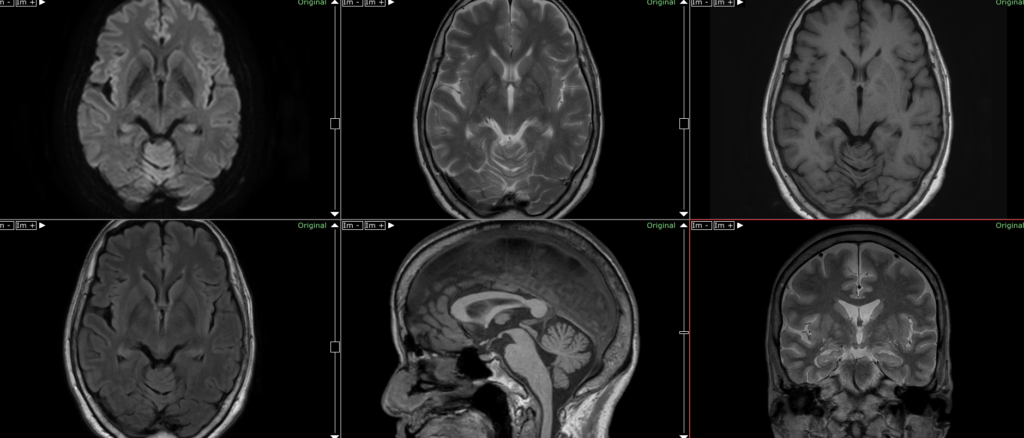

MRI は、脳のスキャンを作成して構造変化を調べる画像検査です。これは、医師が神経疾患を示唆する可能性のある脳の変化を検出するのに役立ちますが、特にパーキンソン病ではありません。

MRI スキャンは、神経疾患を示す可能性のある脳の構造の変化を示すのに役立ちますが、パーキンソン病を特異的に診断することはできません。

診断が不明瞭な場合は、MRI が医師の助けになることがあります。 MRI スキャンは、医師が多系統萎縮、脳卒中、脳腫瘍の証拠など、運動症状を引き起こす可能性のある脳の変化を確認するのに役立ちます。